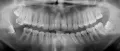

Подскажите, пожалуйста, если будут показания к удалению верхней правой семерки, рядом с которой находится ретинированная и дистопированная восьмерка, стоит ли удалять 2 зуба сразу или поочередно, через какое-то время?

Если удалять сразу, то меньше ли будет лишних манипуляций, разрезов, швов при удалении 8 зуба или на метод удаления ретинированных и дистопированных восьмерок удаление 7 зуба никак не отразится?

Данные зубы необходимо удалять однозначно одновременно, во-первых, потому что Вы один раз испытаете дискомфорт и во-вторых, дело в том, что удаление пройдет наименее травматично, если доктор удалит сначала седьмой зуб, освободит качественный доступ и начнет удалять с более выигрышной позиции восьмерку. Запишитесь к нам на прием к хирургу, у доктора большой опыт удаления данных зубов. Лечащий врач должен иметь опыт, так как ретинированная восьмерка стоит не очень удобно и при неосторожном движении легко улетит в пазуху.